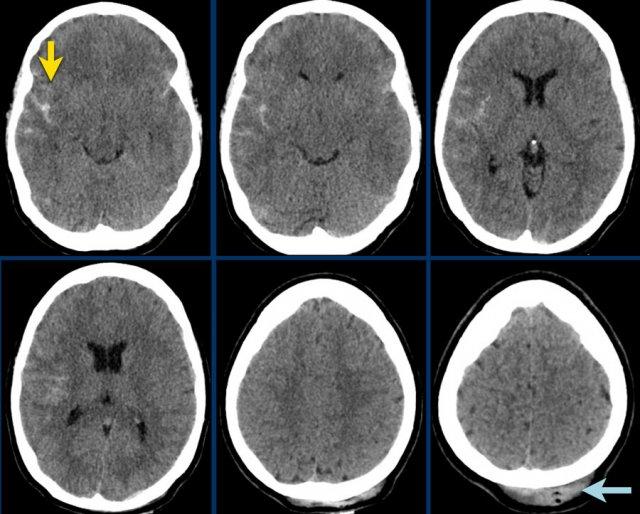

Bệnh nhân này có tụ máu dưới màng cứng cấp tính.

Có sự dịch chuyển đường giữa (hình bên trái).

Bệnh nhân đã được phẫu thuật và khối tụ máu được dẫn lưu (hình bên phải).

Các hình ảnh cho thấy tụ máu dưới màng cứng.

Lưu ý rằng khối tụ máu có cả vùng tăng tỷ trọng và đồng tỷ trọng.

Hình ảnh này có thể gặp trong chảy máu siêu cấp tính, nhưng cũng có thể gặp trong trường hợp chảy máu tái phát.

Có sự dịch chuyển các cấu trúc đường giữa kèm tắc nghẽn lưu thông dịch não tủy, dẫn đến giãn sừng thái dương của não thất bên phải (mũi tên).

Tụ máu dưới màng cứng cấp tính có tỷ trọng cao (máu đã đông), tụ máu bán cấp có đồng tỷ trọng, và tụ máu dưới màng cứng mạn tính có giảm tỷ trọng so với nhu mô não (đồng tỷ trọng với dịch não tủy).